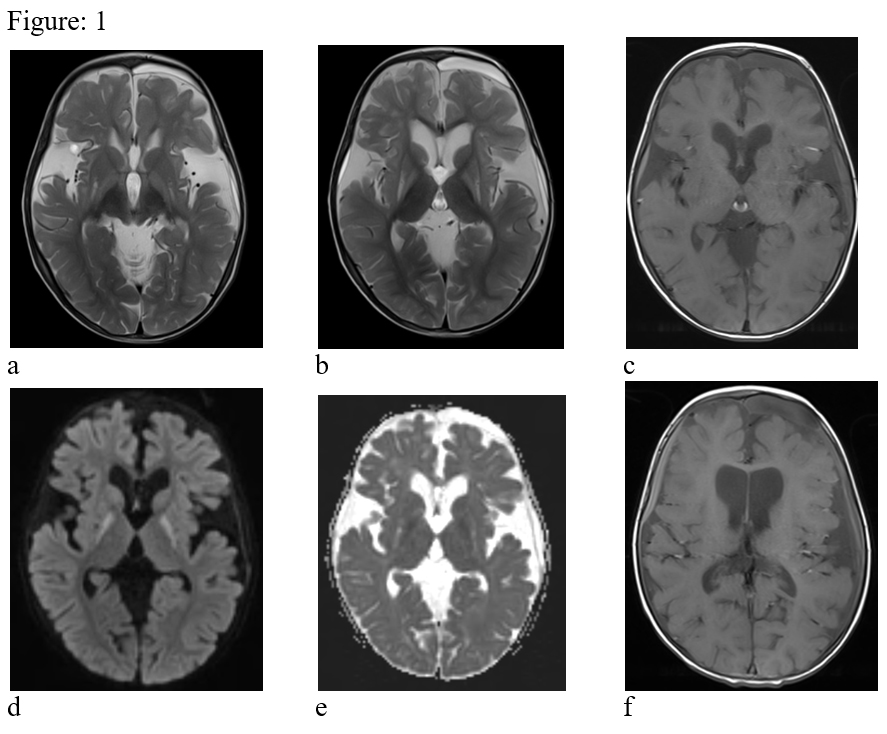

Figure:2- Follow-up MRI after 1 year. There is progressive atrophy of the supra & infratemporal brain parenchyma (a, b & c). The diffusion restriction is not seen in present study (d & e).

Magnetic resonance imaging of the brain is the modality of choice to investigate children with possible GA-1. MRI shows bilateral symmetrical basal ganglia T2 & FLAIR hyperintensity which appear hypointense on T1 weighted images. T2 & FLAIR hyperintense lesions are also noted in substantia nigra, dentate nucleus. Symmetrical T2 white matter hyperintensities are also observed in periventricular & subcortical regions. The lesions in the acute stage show diffusion restriction with progressive atrophy in the chronic stage. No demonstrable susceptibility change or contrast enhancement is seen in the lesions. MR spectroscopy shows presence of lactate peak in acute lesions. Common presentations include enlarged extraaxial CSF spaces predominantly in the anterior temporal regions, wide sylvian fissures & ventricular enlargement. Wide sylvian fissures reveal typical Batwing appearance2. There may be subdural haematoma possibly due to stretching of bridging veins in the enlarged extraaxial fluid space3. Enlargement of optic chiasm with signal alteration in the anterior intracranial visual pathway has also been reported rarely4.